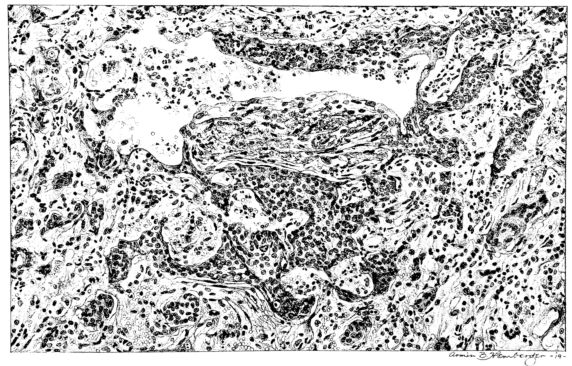

FIG. III. AUTOPSY NO. 90. DRAWING FROM A LESION OF THE TRACHEA (SOMEWHAT OLDER THAN THAT ILLUSTRATED IN FIGURE II). THE MUCOSA IS ENTIRELY LACKING. CONGESTION AND EDEMA ARE THE STRIKING FEATURES IN THE SUBMUCOSA. THE NECROTIZING PROCESS HAS EXTENDED INTO THE MUCUS GLANDS. THIS IS SHOWN IN THE LOWER PICTURE.

The changes are less marked, perhaps, in the trachea than in its finer ramifications. The mucosa is constantly more or less destroyed and large areas, usually focal, are entirely devoid of their epithelial covering. This is replaced by a sparse exudate, composed largely of red blood cells, mucus, a small amount of fibrin, and nuclear fragments (Fig. II). It may dip into the submucosa for a short distance, but usually these indentures are associated with the ducts of the mucous glands into which the inflammatory reaction extends. A more striking feature than the exudate, however, is the edema and the congestion of the submucosa. The loose areolar tissue of the submucosa is spread widely apart, and throughout it distended blood vessels are very conspicuous. Occasionally such a vessel is broken and actual hemorrhage appears in the submucosa. Occasionally, too, the inflammation extends down the duct to the mucous gland itself, and here, also, aplastic inflammatory reaction is evident, inasmuch as the acini now stain intensely red with the cells undifferentiated from each other and specked here and there by broken remains of the dead nuclei (Fig. III). After the disease has continued for a short period, even at the end of five or six days, some regeneration of the epithelial lining may be seen (3) (Fig. IV). But despite this, the acute picture persists, and there goes on, side by side, an attempted repair characterized by epithelial regeneration and the same evidence of acute change. Since the lesion is essentially a superficial one, scars or contractures of any extent are not encountered in the trachea, even in examples of the disease that have ended fatally only after many weeks.[4]

15There is considerable evidence to support the view that the disease spreads from bronchus to bronchus, and in keeping with this view, various stages in the inflammatory processes are more readily determined in these smaller structures than in the trachea. Furthermore, it must be emphasized that even the mildest and the most extreme of these stages are not infrequently encountered in the same lung. The earliest lesion is manifested by an increased homogeneity of the protoplasm of the epithelial lining of the bronchus. The cell protoplasm loses its normal granulation and the nucleus, somewhat darker than usual, becomes conspicuous on a red base (Fig. V). In the lumen of such a tube a serous exudate, perhaps mixed with mucus, is encountered, and there is some spreading apart of the surrounding muscular tissue with engorgement of the vessels. This picture merges gradually into one where the epithelium appears as a homogeneous, red-staining ribbon, devoid of nuclei, often exfoliated, in part at least, from the underlying submucosa (92). The change is traceable through the larger bronchi, even to the ducti alveolares, and not infrequently, bacteria, either as a diffuse, minute dotting or in the form of circumscribed, colony-like formations, are spread through the red, ribbon-like strand (Fig. XVI). With the exfoliation of the epithelial lining, the submucous vessels become more and more conspicuous and may bulge into the lumen of the tube (Fig. VI). That they actually weep into the lumen is proved by the presence of red blood cells in the exudate, now rich in mucus, broken-down nuclei, and desquamated cells. The necrotizing process may not extend deeper than the epithelial lining as is the status described above (140, 162), but it also frequently involves the underlying submucous and muscular layers, so that these lose their identity and stand out as homogeneous masses, in which fragmented nuclei and bacterial accumulations are prominent. Such deeper necrotizing areas may be focal (Fig. VII), or may involve the entire circumference of the tube (Fig. VIII). Occasionally, the epithelium, now dead and staining homogeneously, is lifted from the underlying submucosa in the form of a blister (66), and has very much the same appearance as the well known, early reaction which follows the application of croton oil to the rabbit’s ear. Where this occurs, the submucosa is less involved, as though the necrotizing agent had not penetrated to the same depth and the serous reaction beneath were actually a beneficent exudate. These blisters are in contrast with the deeper areas where the fibrinous mass, mixed with the dead tissue, forms an intensely staining ring or band, which extends through the bronchiolar wall even to the surrounding alveoli.